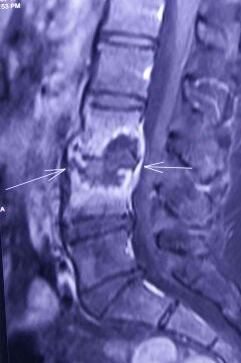

With MRI being available widely, spinal tuberculosis is being detected at early stages now as compared to X-rays. Most of them can be cured well by anti-tubercular medication (ATT). The medication needs to be taken for a long duration (minimum of 6 months – upto 18 months). Drug resistance is a serious problem needing second line medicines and is more difficult to treat. There are special tests like Gene Xpert available now to detect multiple drug resistant tuberculosis.

In some patients with deformity in spine or those with spinal cord compression causing paralysis, surgery to stabilise the spine and decompress the spinal cord/nerves is required. Surgical treatment in right time can prevent spinal deformity/paralysis and help in faster and better recovery of muscle power in those who have developed paralysis.